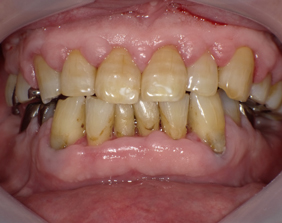

手術前

上下の歯茎が腫れて排膿します。歯磨きするとすぐ出血します。